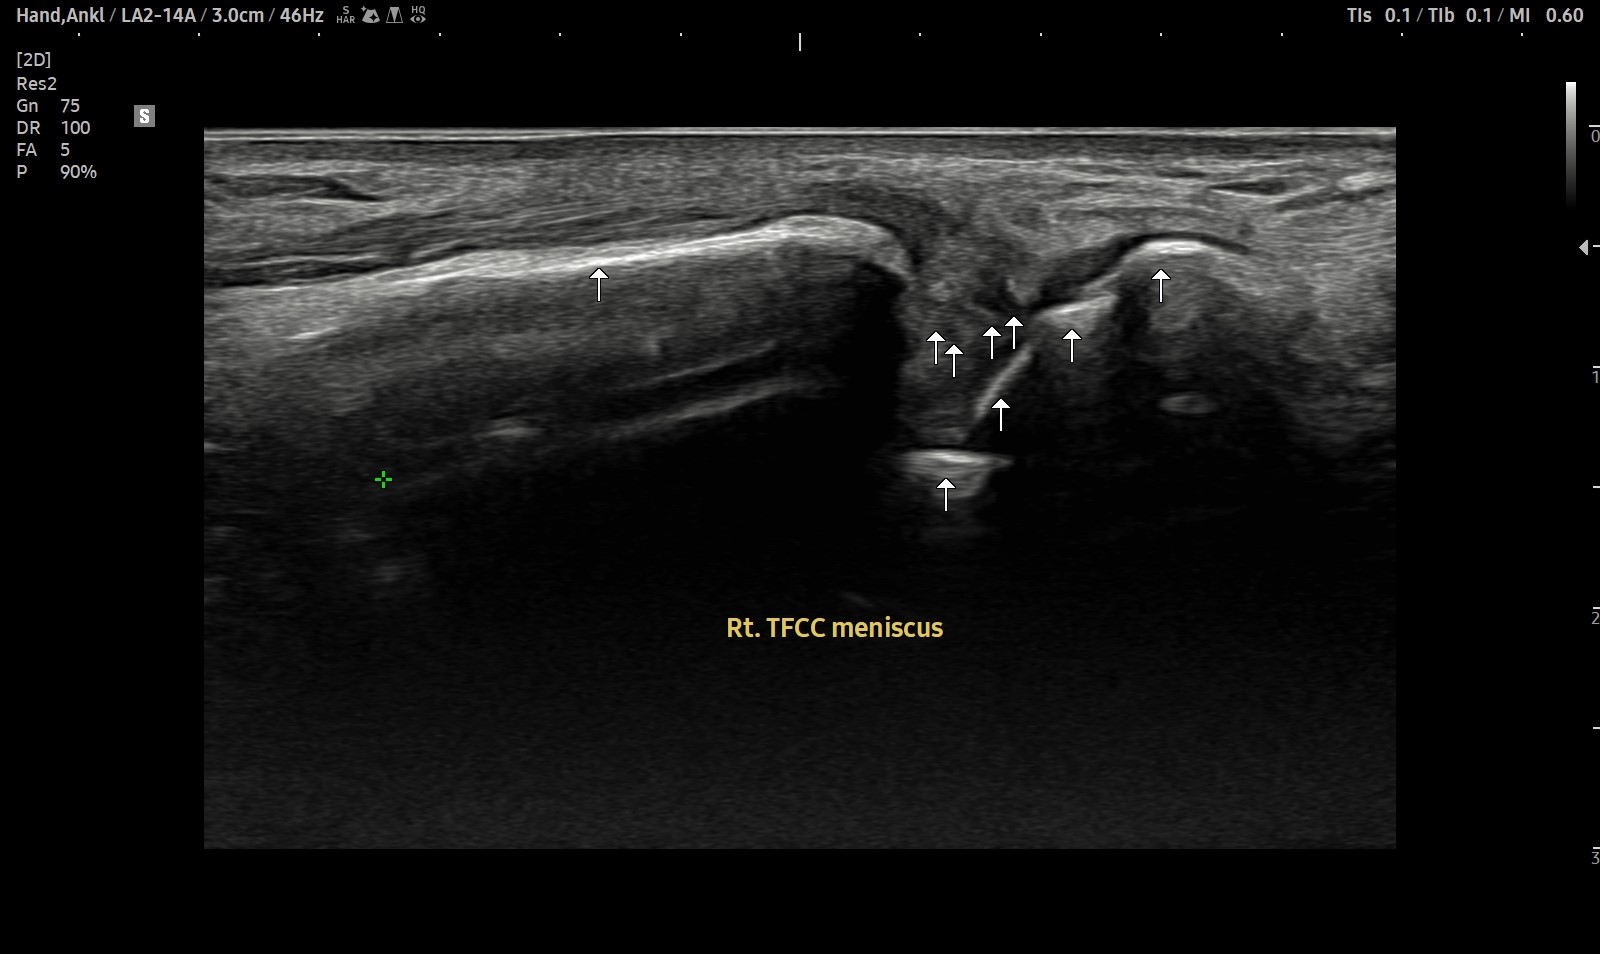

- 치료기간 : 2025 . 2 . 22 ~ 2025. 9 . 20

- 치료횟수 : 4cycle (20회)

8cycle 계획에서 빠른 호전으로 조기 치료 종결 case.

치료 전

치료 후